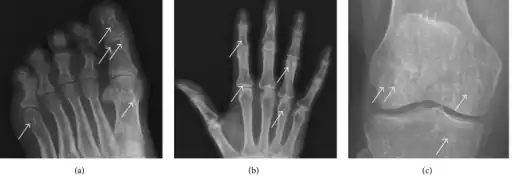

| Osteopoikilosis on an X-ray of the hands | |

In terms of the diagnosis Osteopoikilosis is radiographically evaluated via the presence of multiple symmetrical circular sclerotic opacities [2]

The radiographic appearance of osteopoikilosis on an X-ray is characterized by a pattern of numerous white densities of similar size spread throughout all the bones. This is a systemic condition. It must be differentiated from blastic metastasis, which can also present radiographically as white densities interspersed throughout bone. Blastic metastasis tends to present with larger and more irregular densities in less of a uniform pattern. Another differentiating factor is age, with blastic metastasis mostly affecting older people, and osteopoikilosis being found in people 20 years of age and younger.

The distribution is variable, though it does not tend to affect the ribs, spine, or skull.[3]

a-c)Osteopoikilosis in feet, hand, knee -